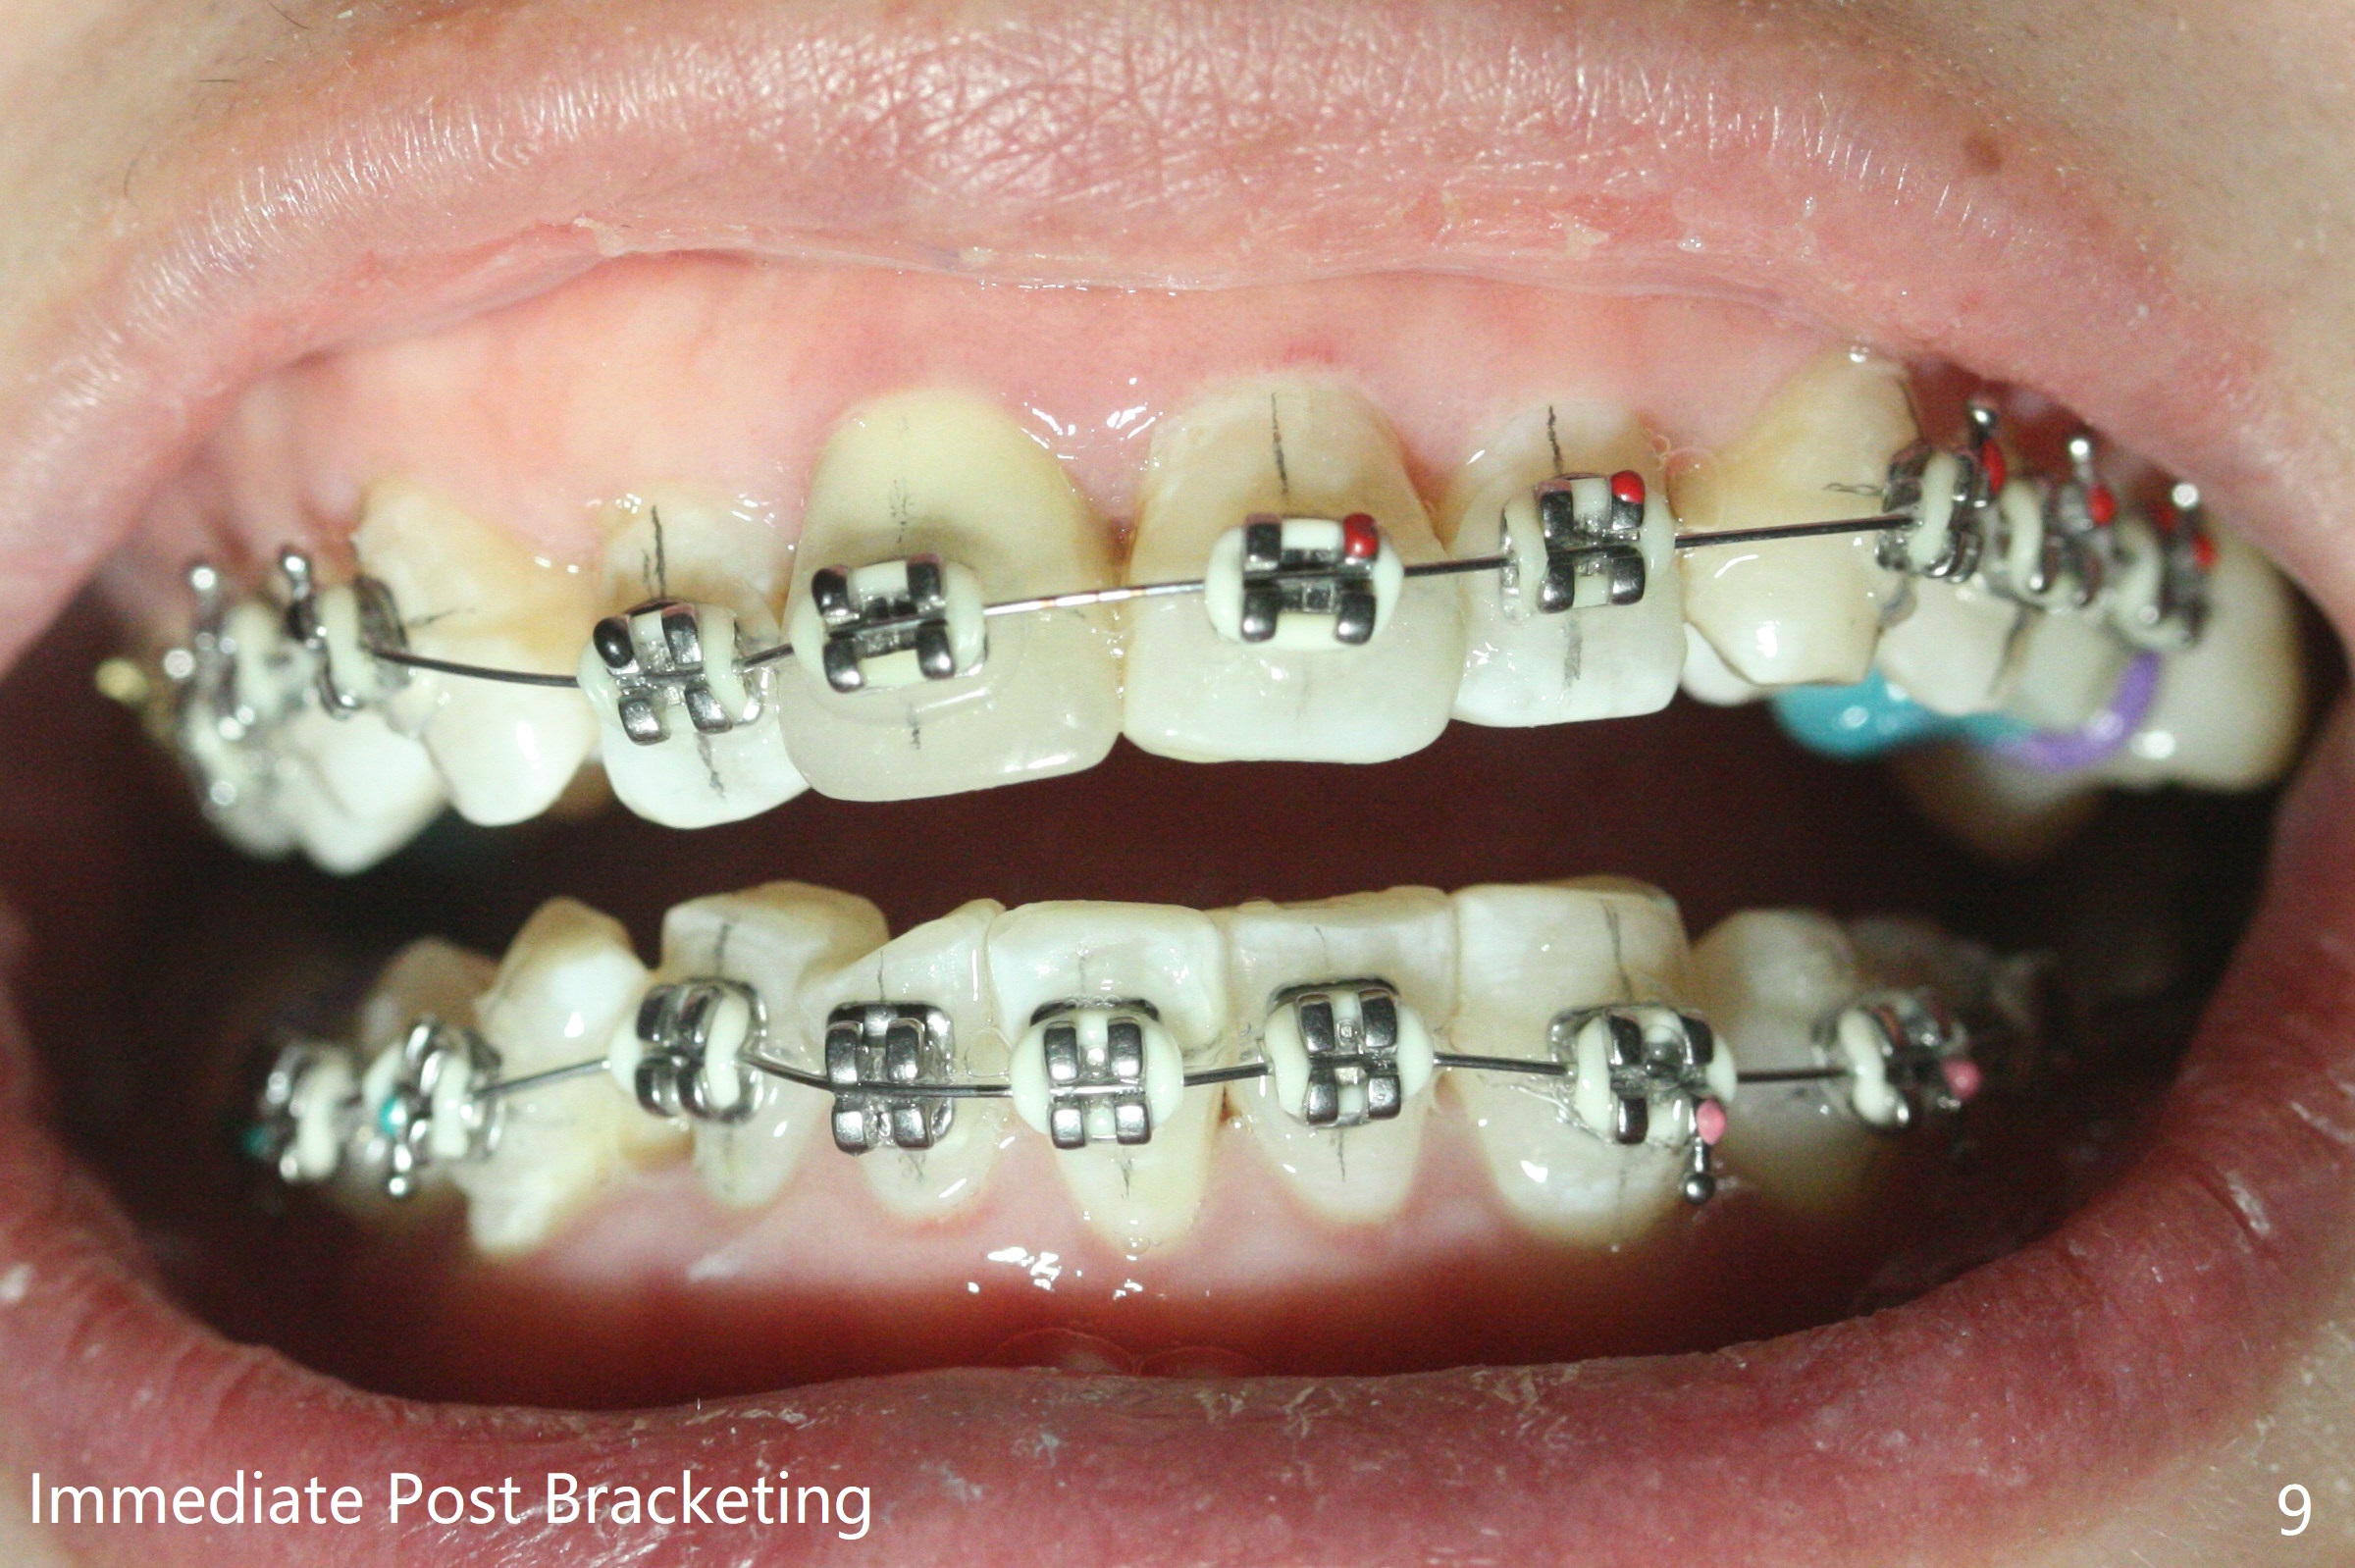

31岁女面部还匀称(图一,二,四,五),但是二类错𬌗严重(图三,六至十),应尽早做二类牵引。压低左上6是 头等大事。磨牙间隙不容易产生,为了避免矫正后磨牙间隙问题,不放置磨牙bands,在右上,右下6,左上6,7放置矫正器,再次使用12niti弓丝。